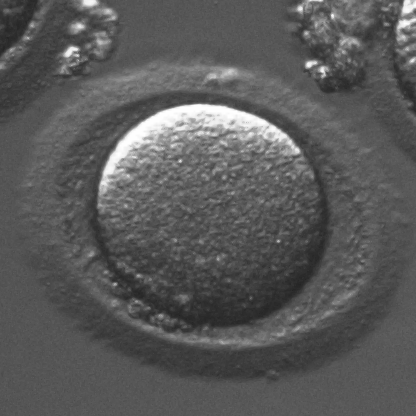

Infertility is becoming an issue for an increasing number of couples. The most common solution, in vitro fertilization, requires embryologists to carefully examine light microscopy images of human oocytes to determine their developmental potential. We propose an automatic system to improve the speed, repeatability, and accuracy of this process. We first localize individual oocytes and identify their principal components using CNN (U-Net) segmentation. Next, we calculate several descriptors based on geometry and texture. The final step is an SVM classifier. Both the segmentation and classification training is based on expert annotations. The presented approach leads to a classification accuracy of 70%.